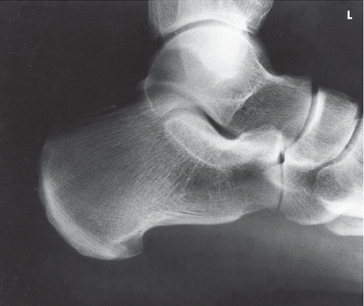

Name this projection.

Axial calcaneus

If the patient is supine, what type of projection is it?

Plantodorsal

How is the CR directed?

40 degrees cephalic (toward heel)

Where does the CR enter?

Plantar surface near 3rd metatarsal base

What anatomy is in profile?

Sustentaculum tali

What joints are seen?

Calcaneocuboid, talocalcaneal (subtalar)

What type of projection is used when the patient is prone?

Dorsoplantar